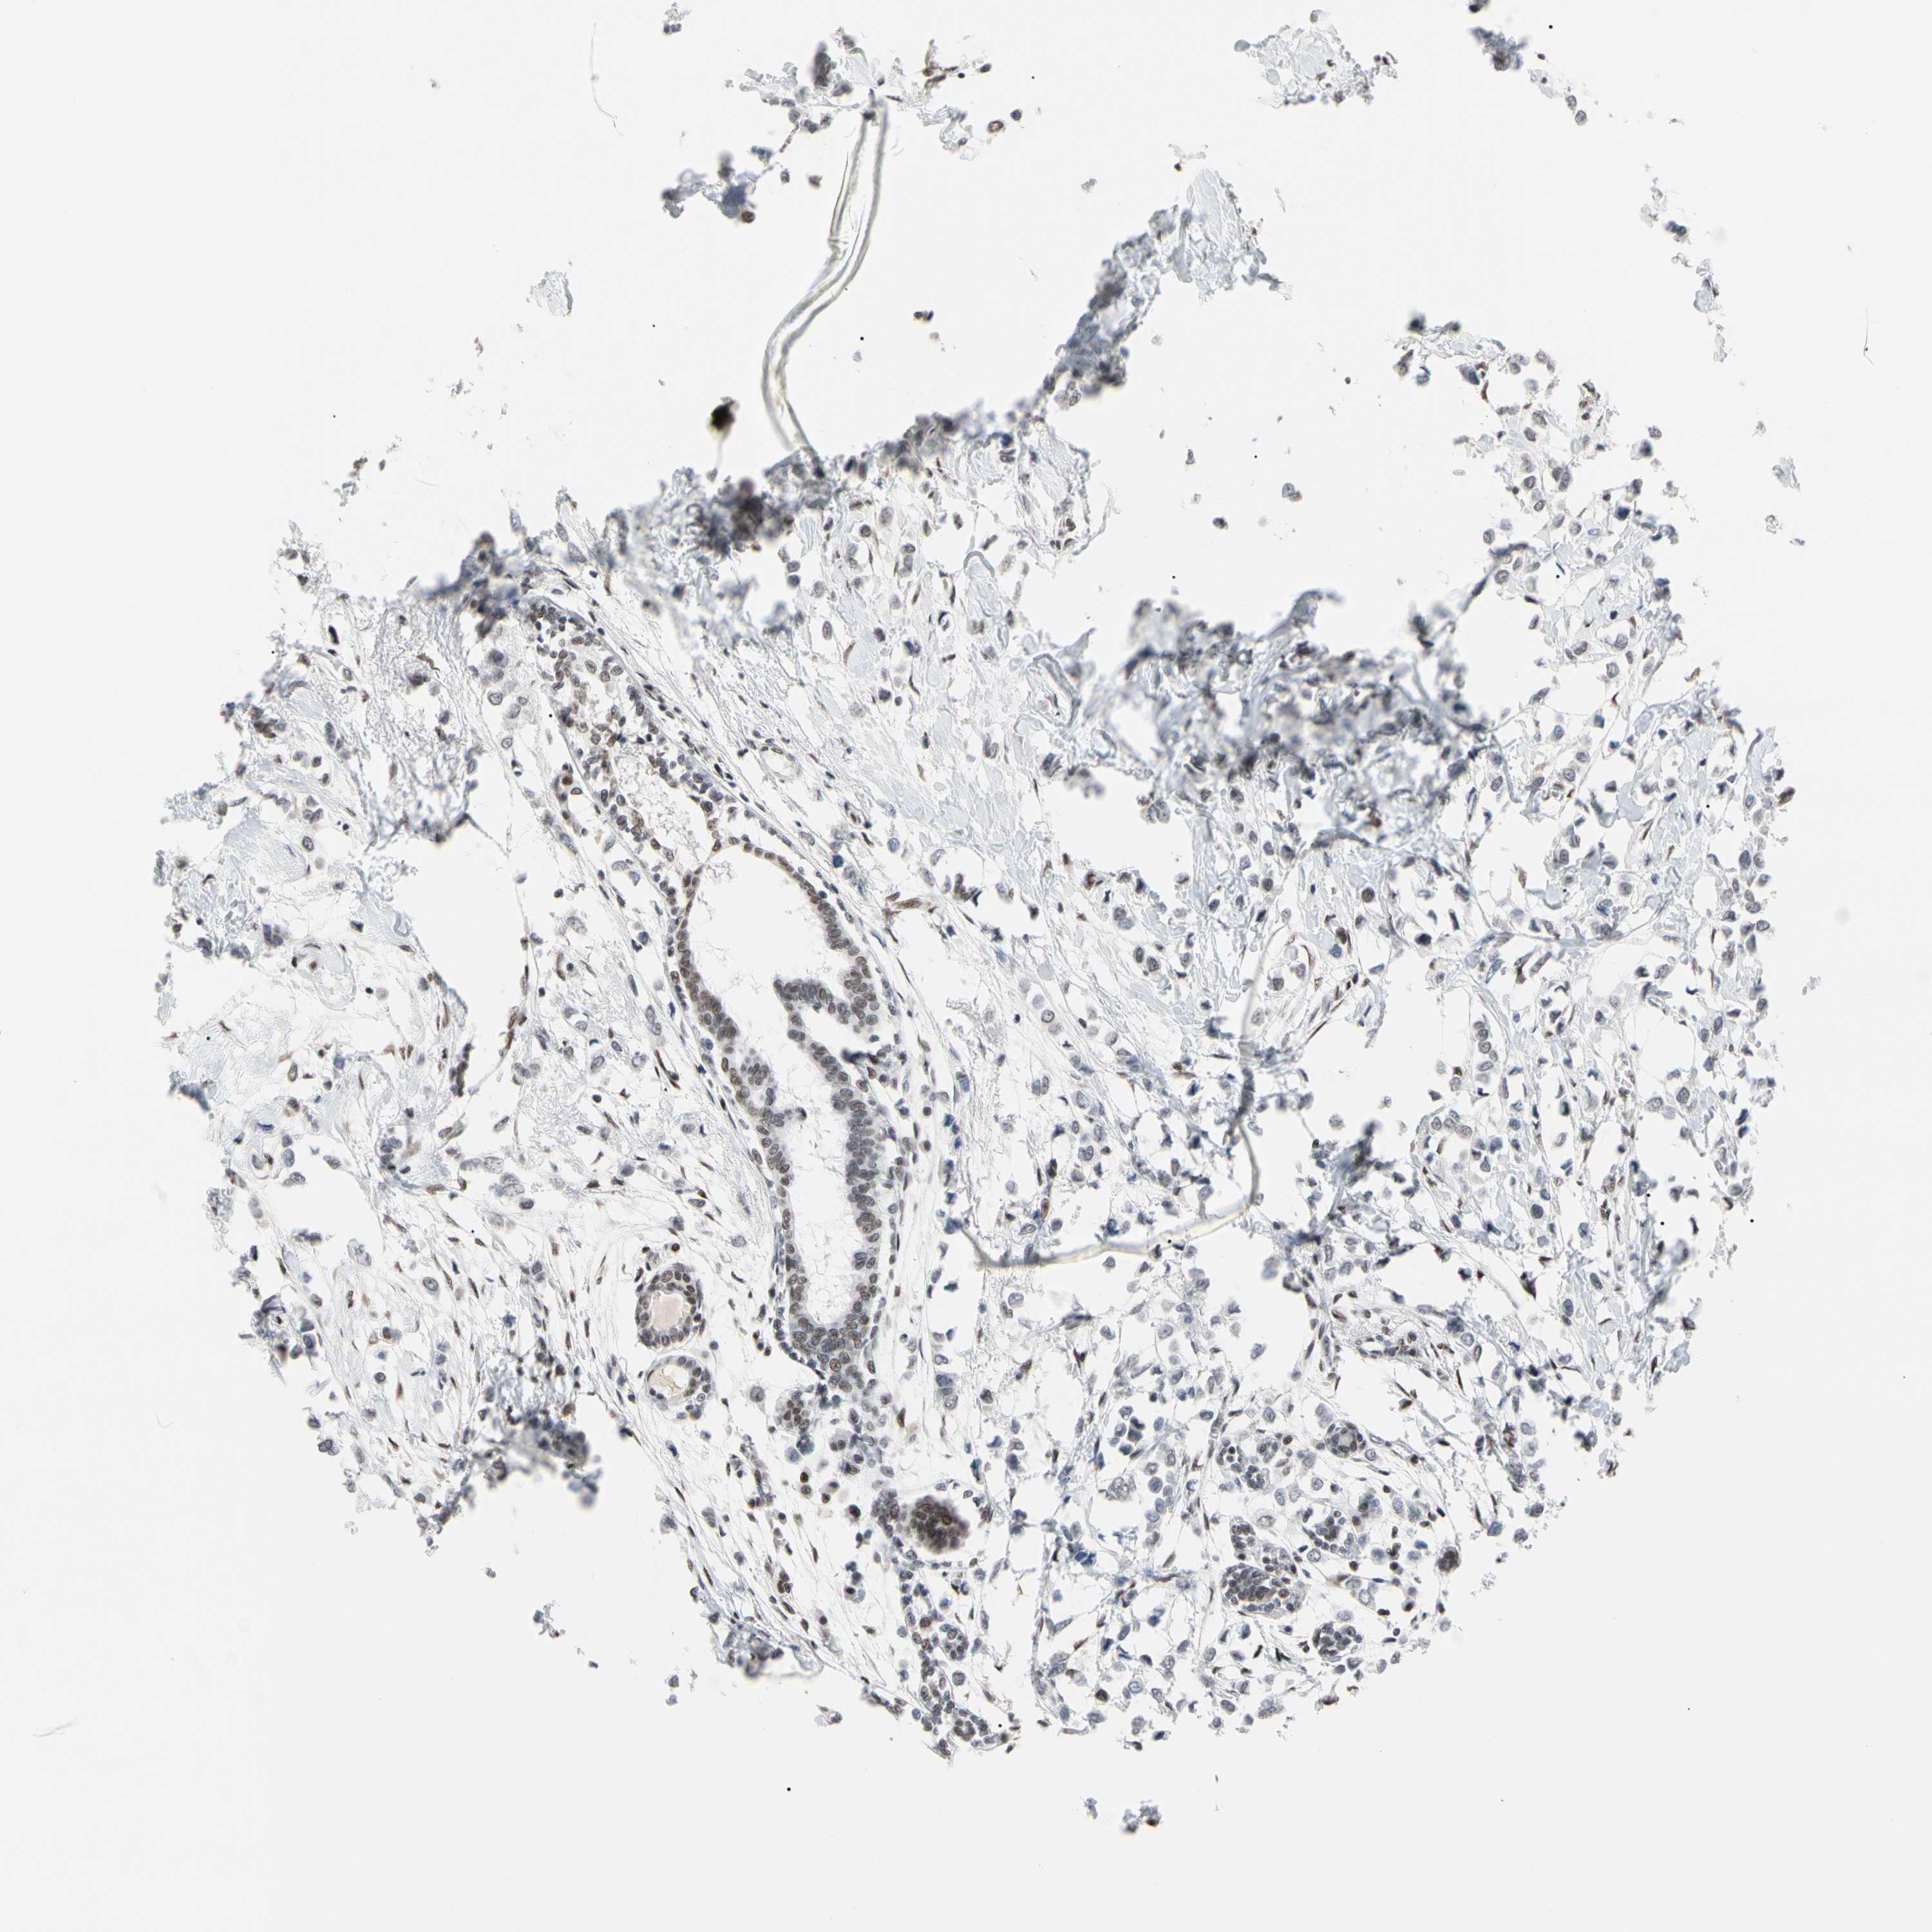

BRCA TCGA BRCA VALIDATION PROTEIN EXPRESSION

ANTIBODIES

AND

VALIDATION